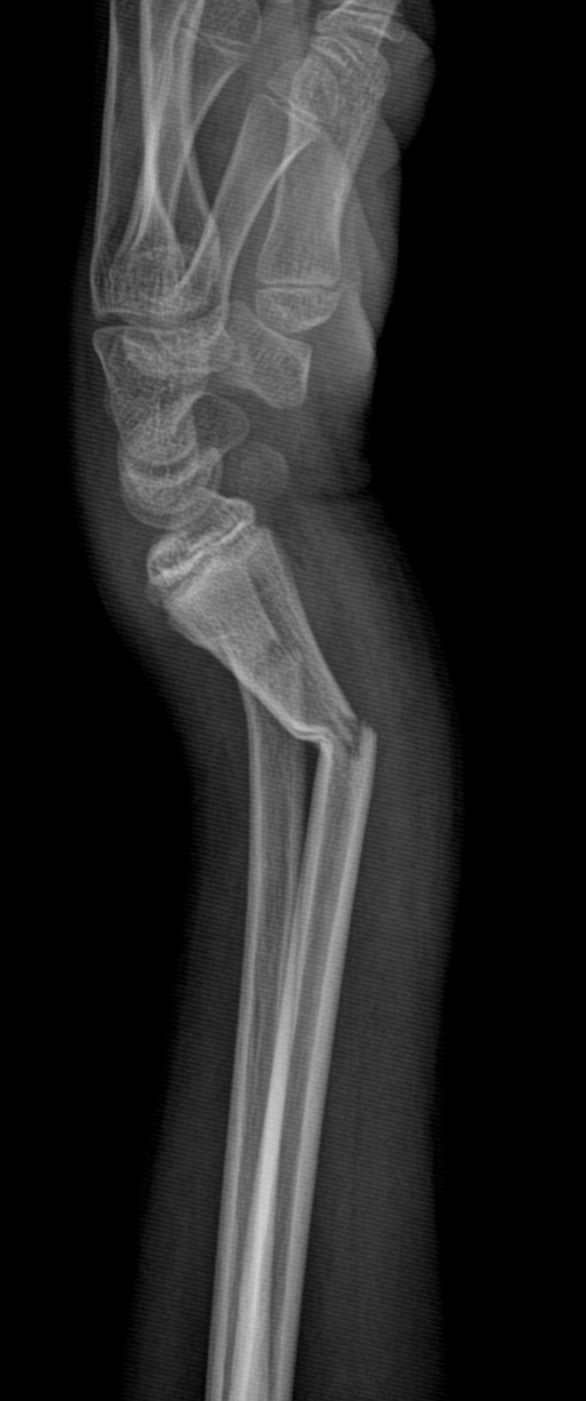

Essa transformação não está apenas nos números. Ela pode ser vista. As imagens que acompanham este texto mostram dois casos atendidos hoje no pronto socorro: crianças com fraturas no antebraço que foram avaliadas, diagnosticadas e operadas no próprio hospital, sem necessidade de transferência. Situações que exigem agilidade, equipe treinada e estrutura funcional.

Em outro episódio recente, uma criança em férias na cidade, com fratura grave de cotovelo, passou por todo o processo, do atendimento à alta hospitalar, em cerca de 10 horas, e já recuperada enviou um vídeo de agradecimento diretamente de Portugal, há dois dias.